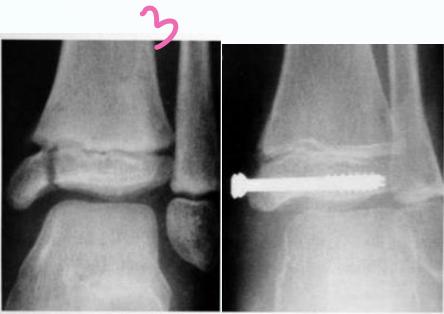

Classification – Salter-Harris

- Type III - Through the physis and extend to intra-articular

Intra-articular (Type III / IV)

- Anatomical reduction and internal fixation

growth plate through and through epiphysis